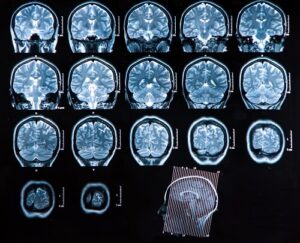

- компьютерной томографии (КТ) и магнитно-резонансной томографии (МРТ) — точные визуальные исследования, предоставляющие достоверную информацию о размере и местоположении новообразования, его структуре, наличии метастатических очагов;